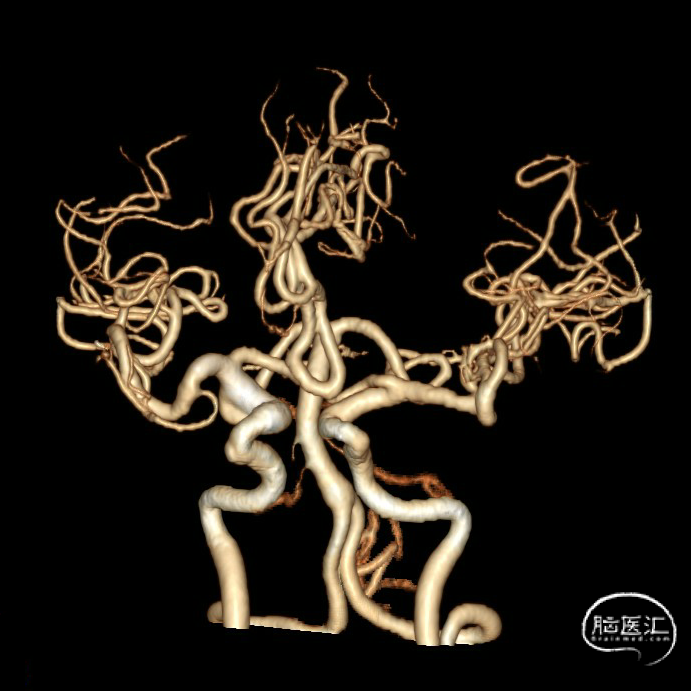

CTA:右侧颈内动脉C7段动脉瘤。

老年女性患者,检查发现右侧颈内动脉C7段大动脉瘤,动脉瘤直径大于10mm,形态不规则,宽颈,手术指征明确,既往高血压、肿瘤病史,首选微创介入手术,术中造影证实动脉瘤直径大于10mm,绝对宽颈,形态不规则,局部仔瘤改变,右侧脉络膜前动脉从瘤体发出;微创介入血流导向装置是较优选择。

DSA造影:

大动脉瘤的微创介入栓塞治疗存在需要支架辅助,瘤颈处理困难、复发率高、费用高等难点;血流导向密网支架置入是较优选择,操作相对简单,不用填塞弹簧圈,完整覆盖瘤颈,远期明显降低再复发概率。本病例为右侧颈内动脉C7段累及脉络膜前动脉的大动脉瘤,该部位解剖结构复杂,周围血管分支多,在操作过程中要避免损伤正常血管,否则会引发严重脑缺血事件;其次,动脉瘤与脉络膜前动脉关系密切,既要处理好动脉瘤,又要保证脉络膜前动脉的血供不受影响,这对手术操作精度要求较高;再者,瘤颈的处理较为棘手,瘤颈较宽,传统弹簧圈栓塞难以达到理想效果,且容易复发。血流导向密网支架置入可解决这些问题,术前需借助3D-DSA,全面评估动脉瘤大小、形态、瘤颈宽度、与周围血管关系,制定精准手术方案。操作时,微导管的到位是关键一步,要在路径图引导下,小心、轻柔操作,避免刺激血管引发痉挛或动脉瘤破裂。释放支架过程中,要注意关注支架位置和贴壁情况。释放后要通过多角度造影,确认支架完全覆盖瘤颈,且支架内血流通畅,分支血管未受影响。同时,术后要密切观察患者神经功能变化,预防血栓形成、血管痉挛等并发症,及时给予抗血小板、解痉等药物治疗。